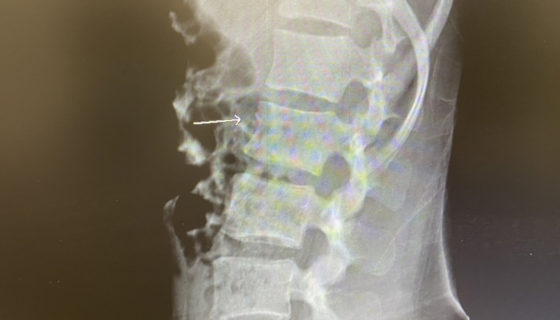

カテゴリー 日常 厚木 投稿者 作成者: Kiyoshi 投稿日 2021/01/28 厚木 へのコメントはまだありません 久しぶりの厚木の工場。 門を開けて入って良いと聞いてたのに 南京錠がかかってて入れず。 7時半頃行くと来たところで すぐに卸してくれた。 スイスの薬局での診断書を作ってもらい 1日早く出られる事になった。 しかし2週間自宅で隔離は変わらず 病院は決められた場所しか行けないらしく 空港近くで診断。 レントゲン。 折れてるのがよくわかる。 ← 東金 → 富士 コメントを残すメールアドレスが公開されることはありません。 * が付いている欄は必須項目ですコメント * 名前 * メール * サイト